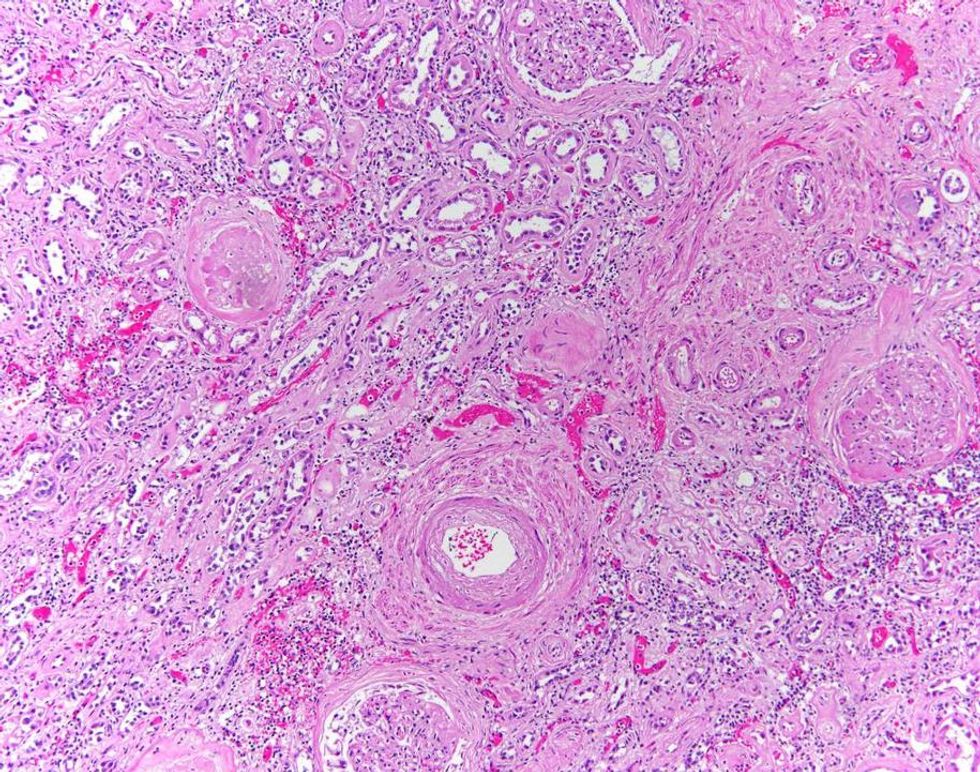

Small bowel

The majority of the images are representative of what Dr Hamel sees when performing autopsies. The colours are diagnostic colours which are added to slides to help define human tissue.